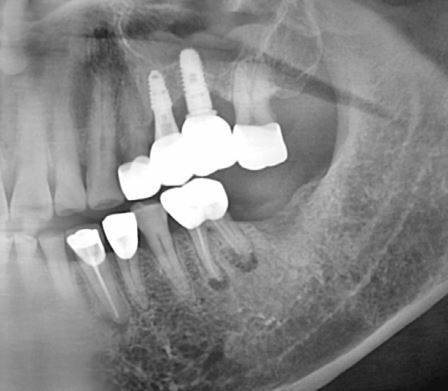

임플란트 식립 술전, 술후 사진, 60대 남성 (2023.07)

임플란트는 아주 좋은 방향으로

좋은 고정을 나타내며 식립되었습니다.

환자분 흡연을 가끔 하긴 하시지만, 당뇨병은 없으시기 때문에

한번에 뼈와 임플란트가 잘 유착되길 기대해봅니다^^